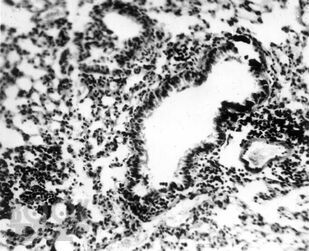

Книга посвящена вопросу лечения пелоидами очень распространенной патологии – болезней органов дыхания: острой пневмонии, хронического бронхита, бронхиальной астмы. В эксперименте и на клиническом материале показано воздействие грязелечения на воспалительный процесс, состояние иммунитета и адаптации, бронхиальную проходимость. Дана эффективность назначения иловых сульфидных, сапропелевых грязей и торфов у больных с болезнями органов дыхания. Рассмотрены вопросы переносимости этими больными грязелечения и возможности оптимизации его результатов. Приведены материалы по использованию средства «Тонус плюс», сочетающего в себе биологически активные компоненты двух видов грязей, набора трав и солевых носителей. Книга предназначена для физиотерапевтов, курортологов, пульмонологов, врачей общей практики. Это первый обобщенный труд по использованию грязелечения в пульмонологии. Его данные могут быть использованы не только в практической работе врачей, но и в учебном процессе при подготовке физиотерапевтов и курортологов.